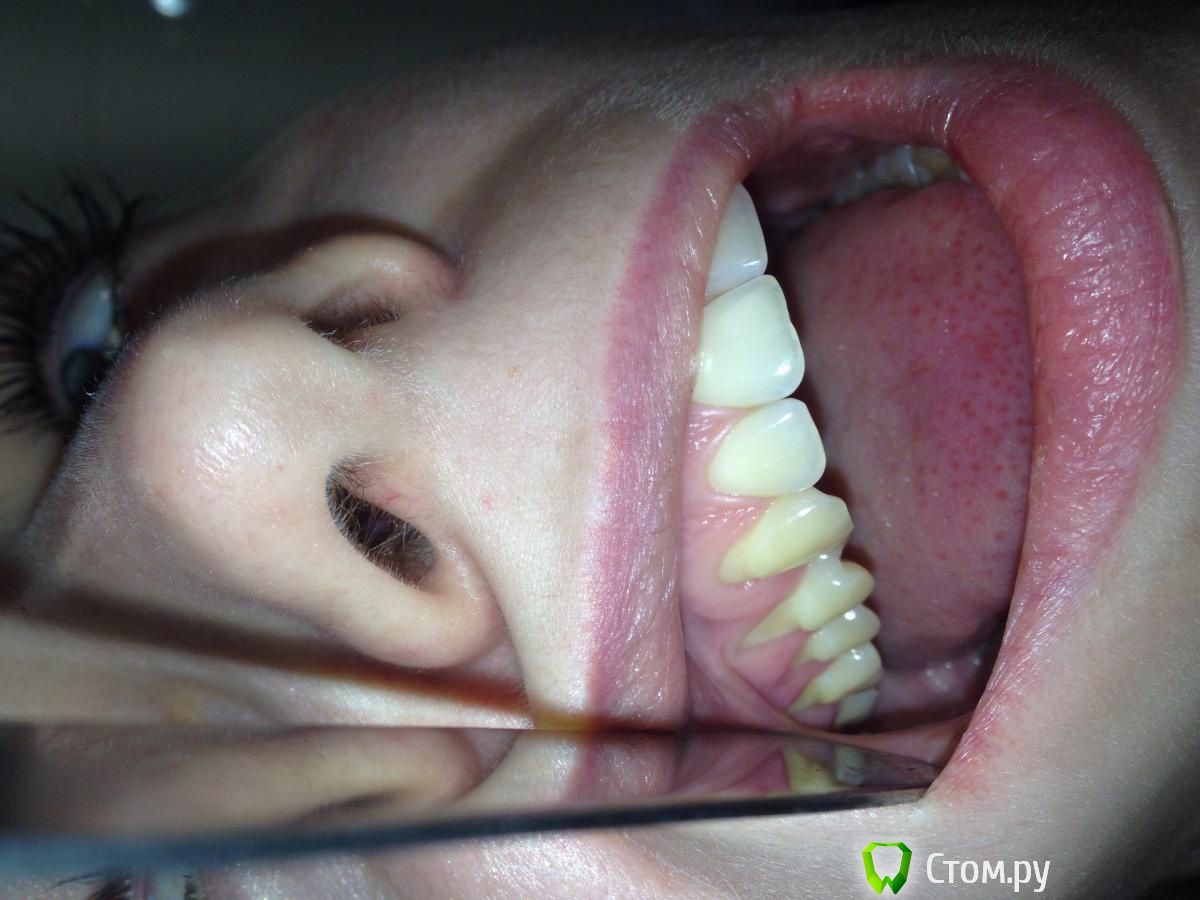

bizkit090 Опубликовано 30 ноября, 2014 Поделиться Опубликовано 30 ноября, 2014 Добрый день уважаемые коллеги!!! Помогите с выбором тактики лечения данного клинического случая. Какую методику выбрать, чем обработать корни, откуда лучше взять трансплантат..Заранее благодарен Ссылка на комментарий

diesel87 Опубликовано 30 ноября, 2014 Поделиться Опубликовано 30 ноября, 2014 А какая причина рецессий и кд? Ссылка на комментарий

Dr.Aubov Опубликовано 1 декабря, 2014 Поделиться Опубликовано 1 декабря, 2014 По Зуккелли одноэтапно можно при наличии кератинизированной слизистой на уровне ЦЭС с трапецивидным лоскутом смещенным коронарно. Двухэтапно без наличия кератинизированной слизистой оболочки, после первого этапа 3 месяца должно пройти. Ссылка на комментарий